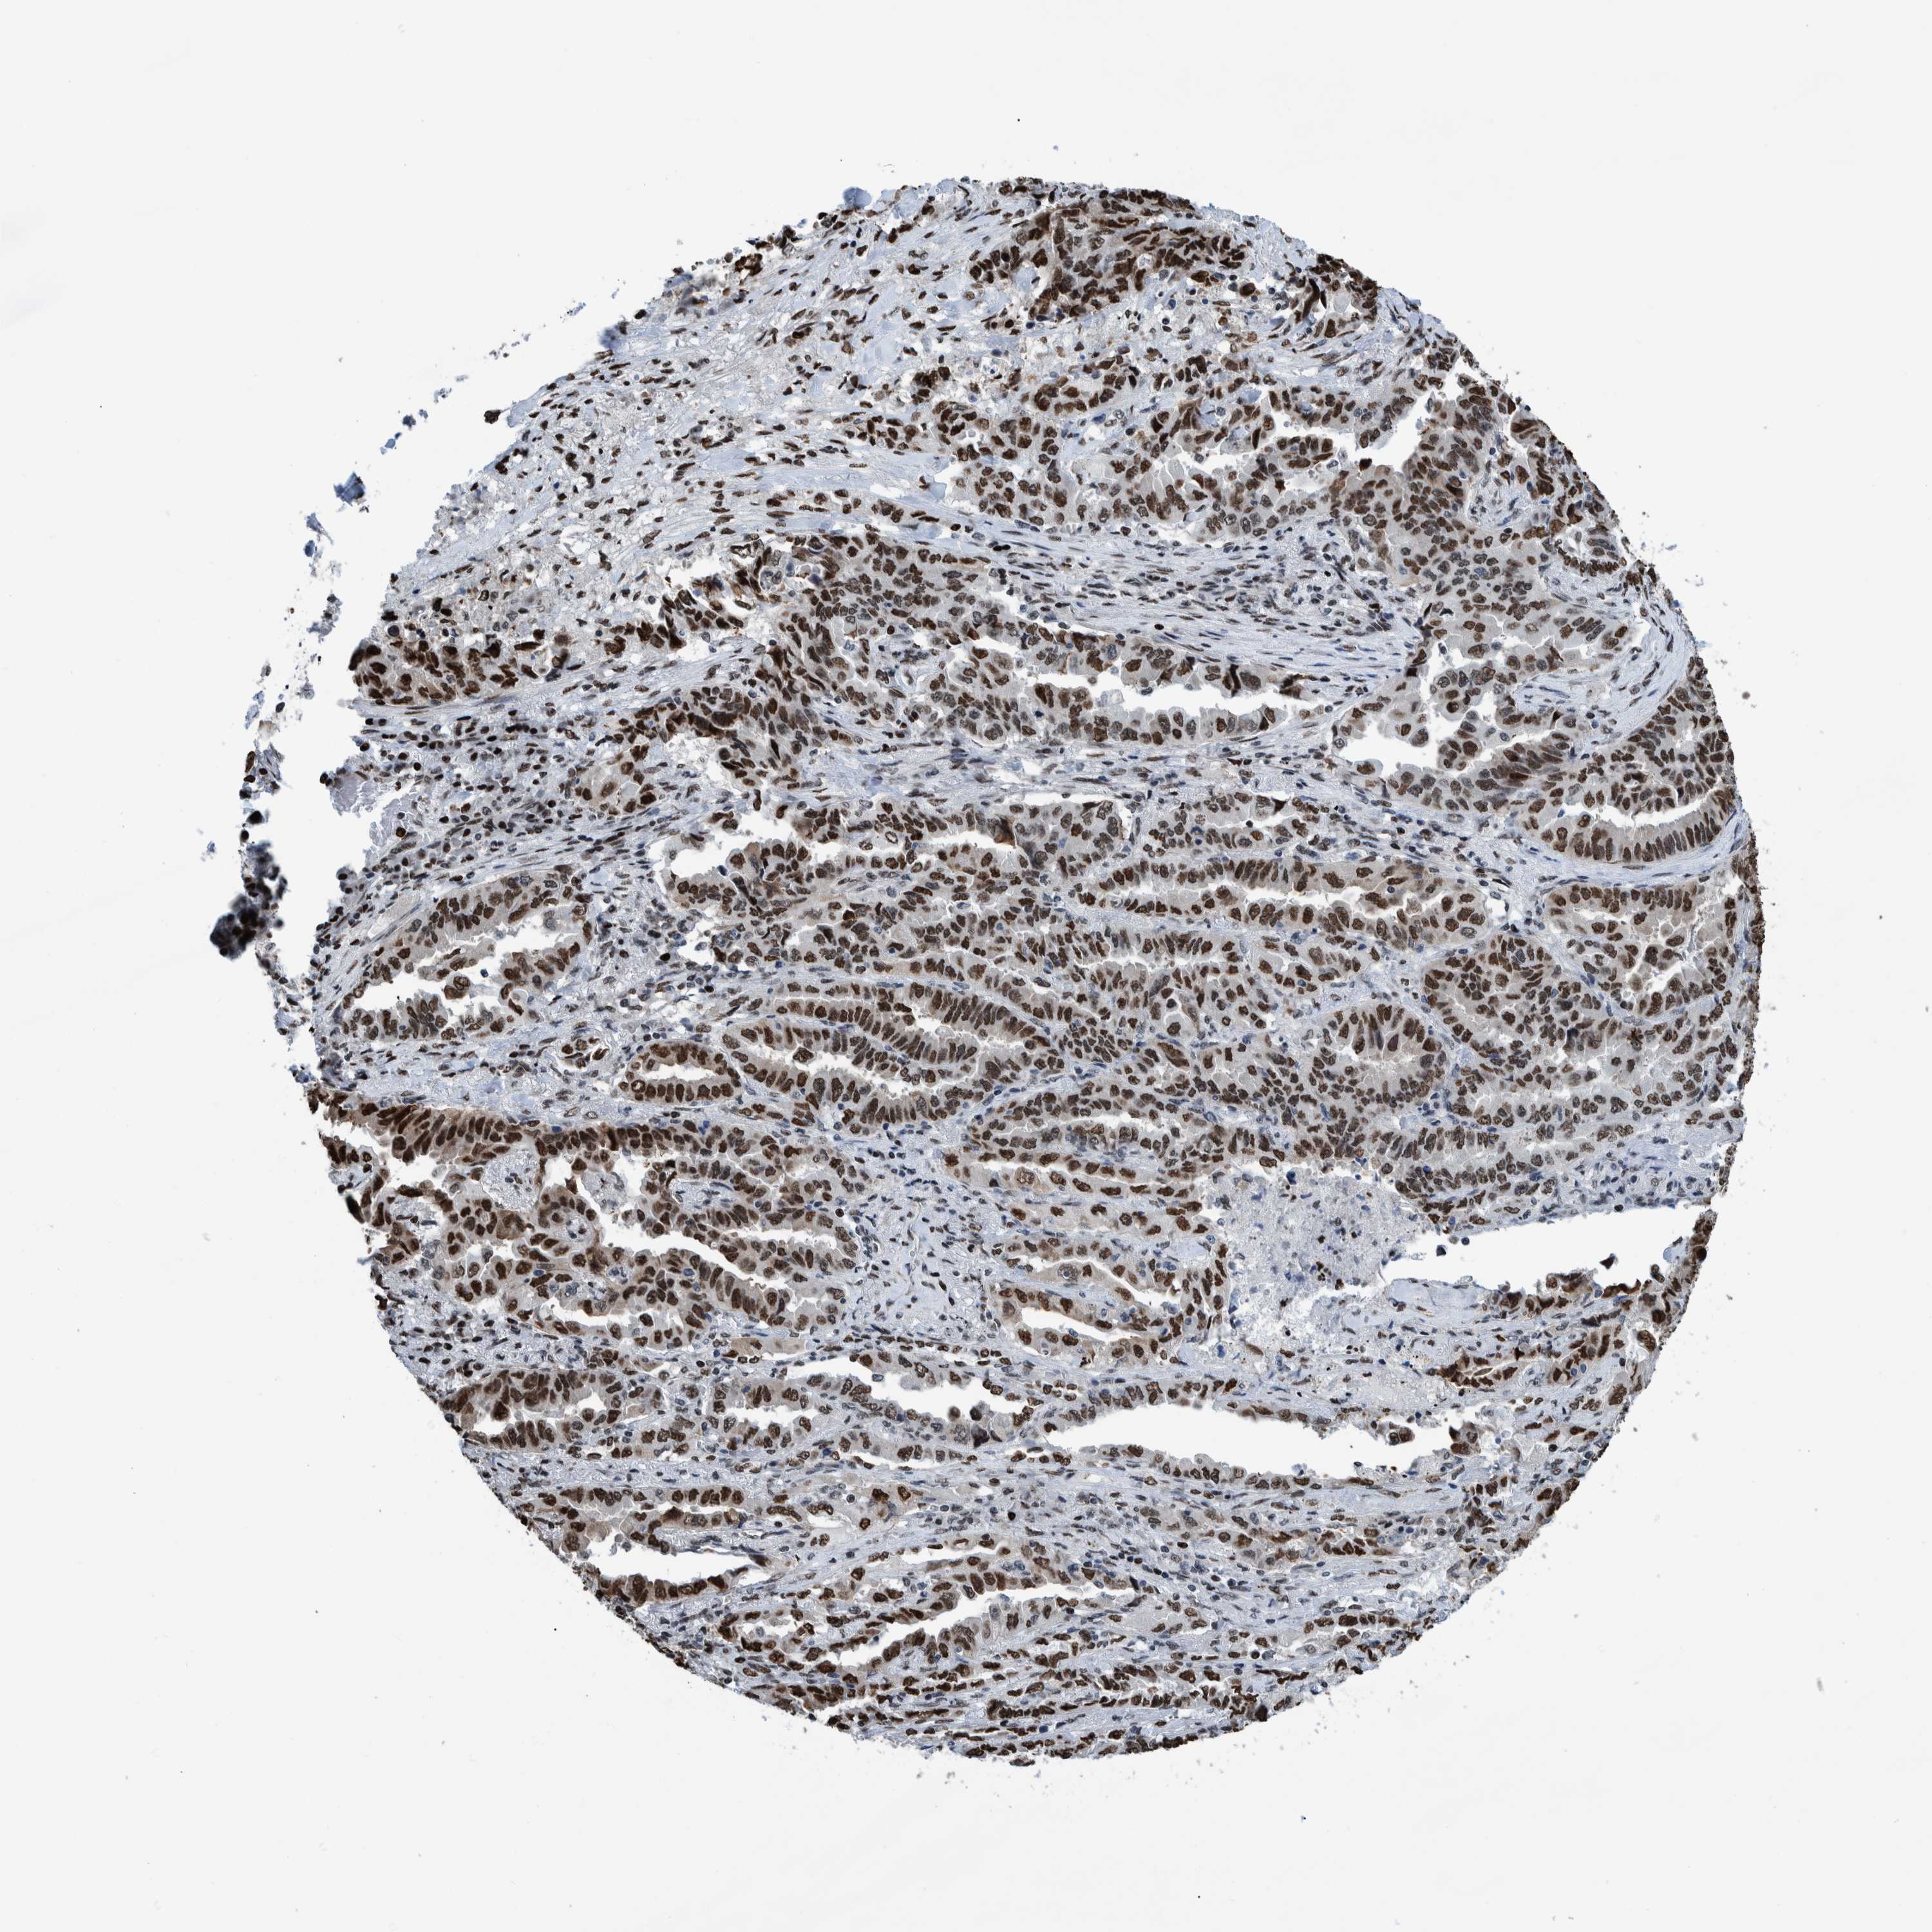

CANCER LUNG CANCER Show tissue menu